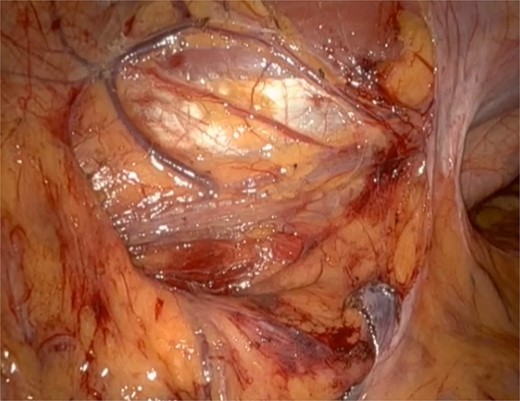

Post tumour removal showed clean base with no active bleeding. No evidence of tissue invasion into peripheral structures.

Histopathological lab reported a 35 mm sympathetic paraganglioma completely excised with clear margins, supported by presence of positive staining for synaptophysin, chromogranin, and S100 seen in sustentacular cells. Postoperative follow-up confirmed normal biochemical parameters with no complications.